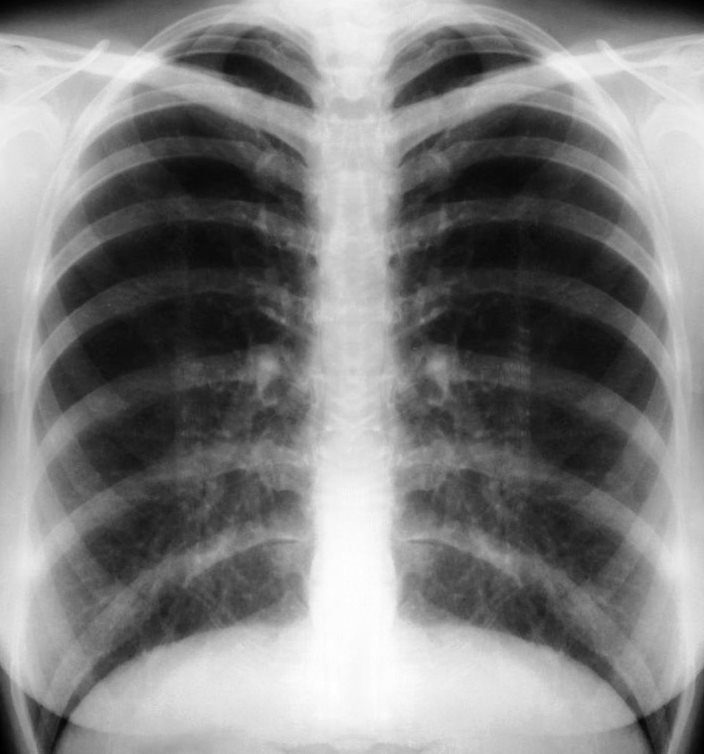

Healty lungs